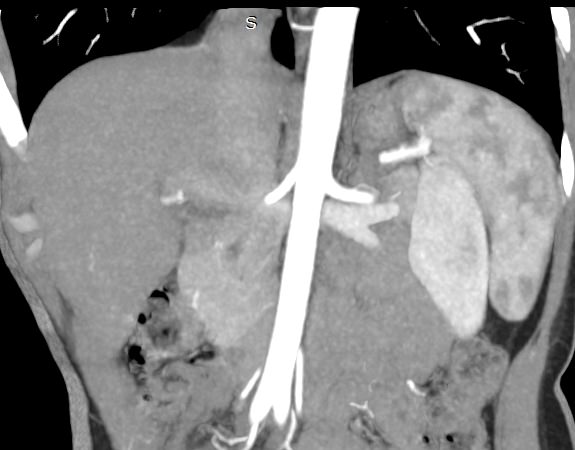

Мультиспиральная КТ сосудов почек (КТ-ангиография) с внутривенным болюсным контрастированием проводится для диагностики патологии почечных артерий. С помощью КТ-ангиографии можно выявить врожденные аномалии развития сосудов почек, диагностировать стенозы (уменьшение просвета) почечных артерий за счет развития атеросклеротических бляшек.

КТ сосудов почек применяется для выявления признаков вторичной артериальной гипертензии, при планировании оперативных вмешательств и для оценки успешности проведенной операции на сосудах. КТ ангиография почечных артерий позволяет оценить их анатомию, выявить добавочные и аберрантные почечные сосуды, определить типично ли они распространяются в ворота почки или заходят в паренхиму через корковый слой.

Чувствительные детекторы улавливают рентгеновские лучи после их прохождения сквозь тело человека. На основании этих данных получаются изображения сосудистой системы почек в мельчайших подробностях. Кроме того, с помощью цифровой обработки данных томограф реконструирует трехмерные модели кровеносных сосудов на уровне исследуемой области. 3D-реконструкции помогают увидеть пространственное соотношение анатомических структур и значительно повышают качество диагностики.

В наших медицинских центрах КТ-ангиография почечных артерий выполняется на новейших мультиспиральных компьютерных томографах экспертного класса TOSHIBA AQUILION. Аппараты сканируют область почек, производя одномоментно множество послойных срезов исследуемой зоны, благодаря этому создаются изображения кровеносной системы высокого качества. Это позволяет проводить точную и достоверную диагностику патологии почечных артерий. При этом за счет скоростного мультисрезового сканирования пациент получает минимальную дозу рентгеновского облучения.